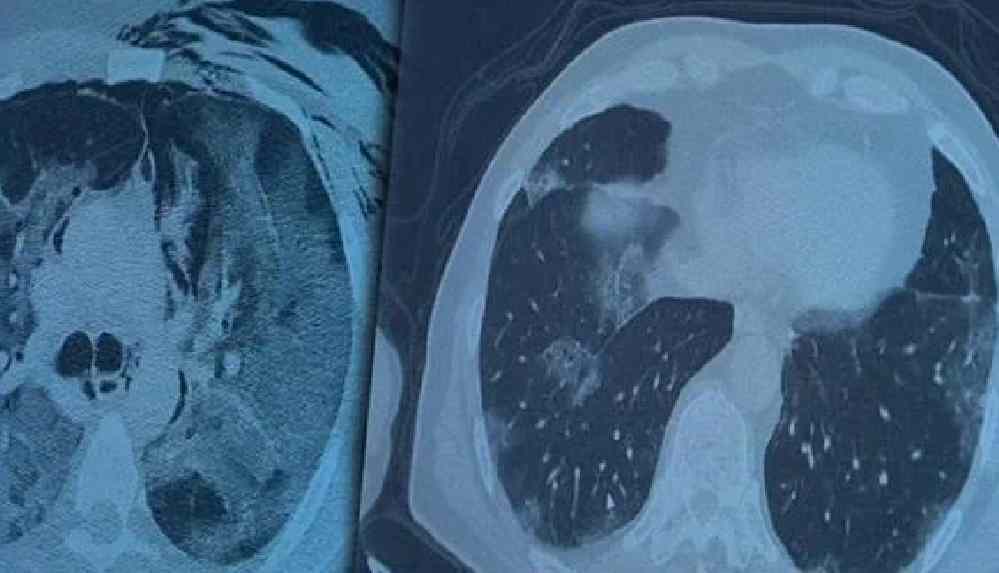

2. doz aşıları tamamlanmış fakat koronavirüs servisinde yatan hastaların akciğer tomografilerini inceleyen Prof. Dr. Özkaya, bu kişilerin akciğer tutulumları olduğu halde hastalığı hafif atlattıklarını söyledi.

Koronavirüs hastalığı genç nüfusta daha fazla görülmeye başlarken Covid-19 aşıları tamamlanan 60 yaş üstü vatandaşlardan bazıları ise koronavirüse yakalanmaya devam ediyor. Göğüs Hastalıkları Uzmanı Prof. Dr. Şevket Özkaya ise aşının gerçek yaşam sonuçlarını gözler önüne serdi. 2. doz aşıları tamamlanmış fakat koronavirüs servisinde yatan hastaların akciğer tomografilerini inceleyen Prof. Dr. Özkaya, bu kişilerin akciğer tutulumları olduğu halde hastalığı hafif atlattıklarını söyledi.

Bugüne kadar aşının etkilerini hep laboratuvar ortamında antikor üretip üretmemesi ile değerlendirdiklerini belirten Prof. Dr. Özkaya, “Vatandaşlarımız aşılarını olduktan sonra ilk gerçek yaşam sonuçlarını yeni yeni almaya başladık. Gerçekten aşı yaptığımızda antikor oluşturuyor ama bu antikor kişiyi koruyacak mı diye merakla beklediğimiz sorunun cevabını, insanlar 2. doz aşısını olduktan bir ay sonra ortaya çıkmaya başladı. Bu hastalar koronavirüsü kaptığında yeni yeni korumaya başladığını anladık. Bir örnek vermem gerekirse, 84 yaşında bir hastamız 2. doz aşısını olduktan sonra eşiyle beraber koronavirüs oluyor. Koronavirüs akciğer tutulumları olduğu halde çok hafif şekilde atlattılar. 65 yaşında başka bir hastamızı göstermek gerekirse, bu hastamız da 2. doz aşısını olmuş ve aradan 1 ay geçtikten sonra antikor da oluşmuş. Bu antikor bu kişiyi koruyacak mı diye gerçek yaşam sonuçlarına baktığımızda, koronanın hastanın akciğerlerine indiği halde çok hafif atlattığını görüyoruz. Eğer bu kişi aşı olmasaydı, hastaneye yatarak daha ağır geçirebilirdi,” diye konuştu.

Koronavirüs servisinde yatan hastaların yüzde 80’inin gençlerden oluştuğunun altını çizen Prof. Dr. Özkaya, “Artık daha genç hastaların mutant virüsle karşılaştıkları için daha ağır geçirdiği görüyoruz. 60 ve 65 yaş üstünü ise aşıyla sigortaladığımızı düşünüyoruz. Aşının gerçek yaşam sonuçlarının olumlu olduğunu görüyoruz. Aşı olanlar virüse yakalandıkları halde çok hafif veya hastaneye yatmadan atlatıyorlar. Şu an servisimizde yatan hastaların yüzde 80’inini genç hastalar oluşturuyor. Artık 60 yaş üstünde çok fazla hasta görmüyoruz. Örneğin (akciğer filmini gördüğümüz) 40 yaşındaki bir hastamız aşılanmadığı için mutant virüse yakalanmış. Akciğerleri çok kötü durumda ve hastanede yatıyor. 24 yaşında bir genç kızımızda ise ciddi akciğer tutulumları görüyoruz. 49 yaşında bir hastamızı ise maalesef çok ciddi akciğer tutulumu ve neredeyse paramparça bir akciğerle yoğun bakımda takip ediyoruz,” şeklinde konuştu.